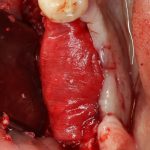

Если на этапе разреза и формирования раны всё сделано правильно, то наложение швов не вызывает особых трудностей. Периостотомия или послабляющие разрезы на периосте не требуются (ни практически никогда не требуются). А сами швы получаются аккуратными и герметичными:

Обрати внимание, что все шовные лигатуры находятся в пределах кератинизированной десны. Это позволяет избежать деформации тканей и лишних рубцов. В наиболее уязвимых местах (около зубов) шовные лигатуры лучше продублировать.

Если бы мне пришлось делать это сейчас, то я бы использовал непрерывный «матрацный» шов. Он удобнее, быстрее в наложении и комфортнее для пациента. Минус — если распускается, то распускается весь. К тому же, его очень неудобно снимать.

Несмотря на то, что уже тогда мы широко использовали непрерывные швы в подобных случаях, здесь я, во-первых, зассал (может распуститься), во-вторых, снятие швов предполагалось в поликлинике по месту жительства пациентки, и мне не хотелось, чтобы там при снятии швов начудили. Как выяснится позже — зря беспокоился.

Неизменно одно — в таких операциях мы использовали и до сих пор используем нерезорбируемые монофиламентные шовные материалы, поскольку они наиболее гигиеничные. Чтобы острые концы нитей не беспокоили пациента, их можно оплавить нагретой гладилкой или гуттаперчевым плаггером.